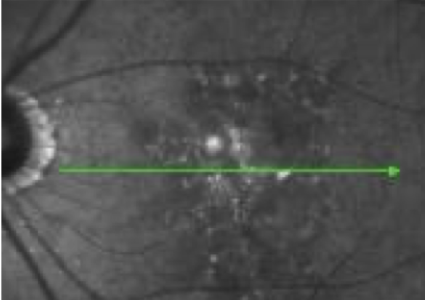

- Patient at baseline has a large area of GA, however, BCVA is relatively unaffected due to foveal sparing

- Within 4 years, OS GA has progressed, but BCVA has only declined slightly as fovea is still intact

FAF

NIR

OCT

Although there is significant atrophy, the fovea remains relatively spared from GA.

Images courtesy of Mohammad Rafieetary, OD, Charles Retina Institute.